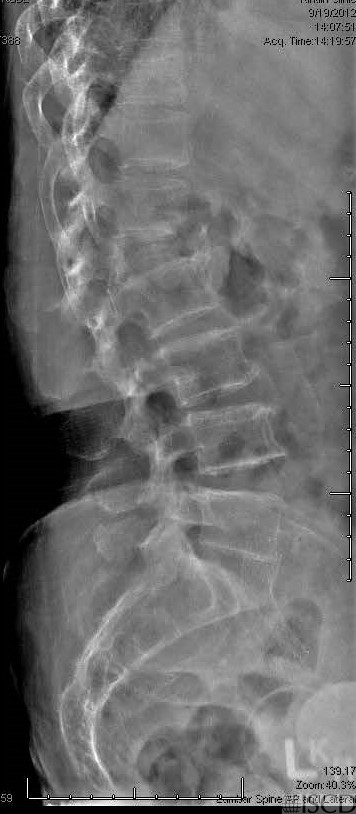

The follow-up DXA scan below shows a L1 fracture. This is accompanying lateral spine radiograph which shows the new L1 compression fracture on follow-up.

The follow-up DXA scan after 2 years shows that the height of L1 is shortened and that there is a compression fracture. L1 is omitted from the baseline and previous DXA scan because of the presence of compression.